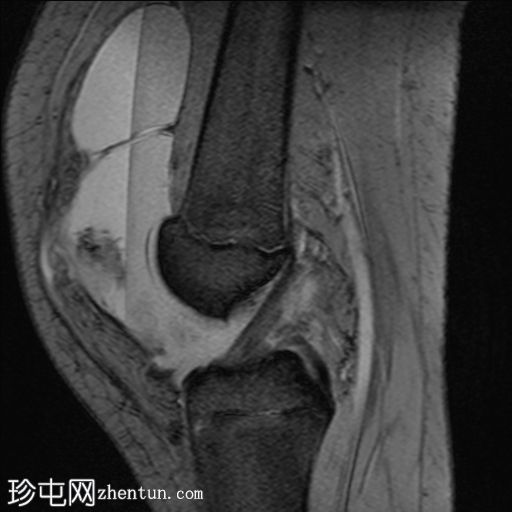

矢状位

T1加权像

PD脂肪抑制序列

梯度回波序列

关节内大量积血,可见血细胞比容增高征。股骨外侧髁前部及髌骨内侧可见挫伤性微骨折。髌骨内侧支持带及髌股内侧韧带水肿增厚。髌骨内侧关节面下关节软骨浸润,提示I期骨软骨损伤。

髌骨外侧隐窝可见游离体,其信号强度与关节软骨一致,提示髌骨关节软骨外剥离损伤。股骨滑车和股骨关节软骨正常。

该病例具有短暂性髌骨外侧脱位复位损伤的特征性表现,包括预期的骨挫伤模式、内侧髌骨支持带/内侧髌股韧带损伤、髌骨骨软骨损伤以及髌骨软骨游离体。